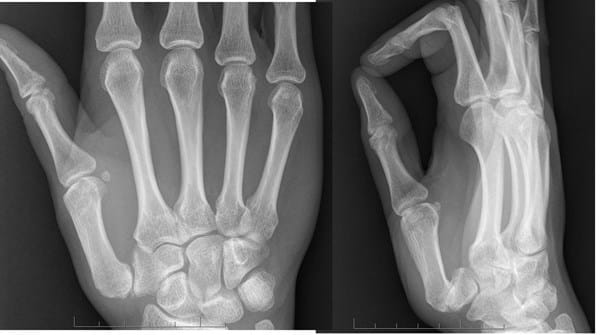

Les adjunto 2 radiografías actuales.

Y yo me pregunto, desde mi total ignorancia en la materia: ¿No se podría colocar el trapecio en una posición correcta? O bien, ¿sustituirlo completamente por una protestis?